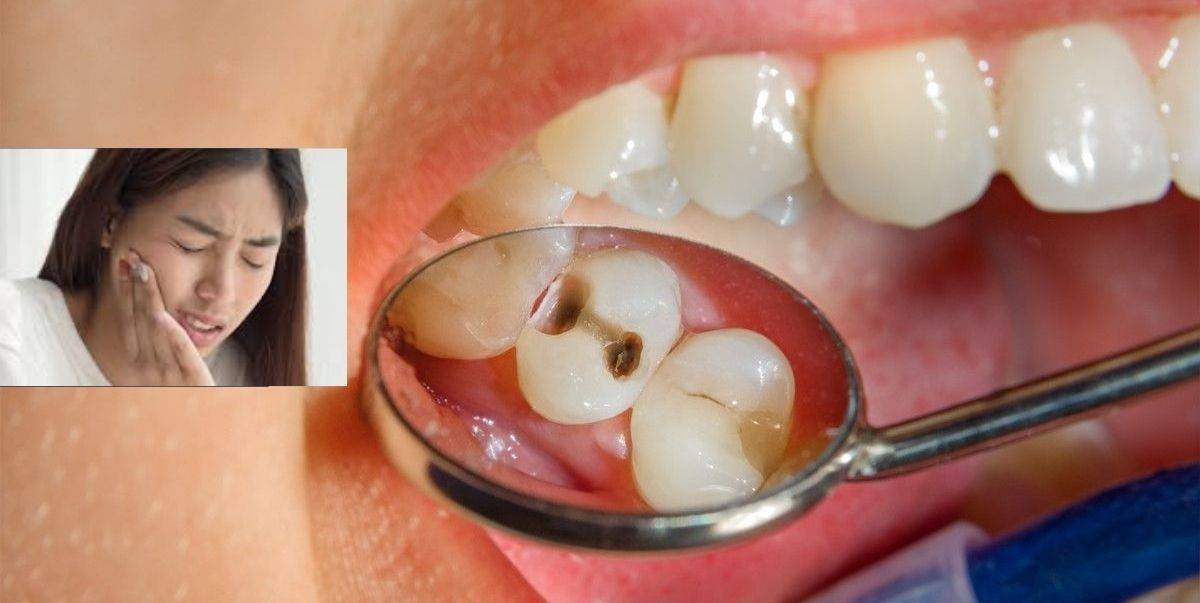

Gigi Berlubang Punca Faktor Risiko Simptom Dan Rawatan

Bunga dengan empat atau enam helai mahkota bunga oleh masyarakat tertentu. Untuk mengatasi sakit gigi. Hal ini membuat gigi lansia menjadi lebih mudah berlubang dan lebih rentan terhadap penyakit gusi.

3 Rekomendasi Rumah Sakit Paru di Indonesia. Daun sirih mengandung banyak agen antimikroba yang secara efektif memerangi sejumlah bakteri yang tinggal di mulut yang memicu bau mulut masalah gigi berlubang plak dan kerusakan gigi. Soloraya Belajar Tempa Keris di Museum Keris Nusantara Solo Prosesnya Bisa.

3 Bahan Alami Paling Jitu untuk Mengobati Gigi Berlubang. Seorang anak pengungsi Somalia yang mengalami kekurangan gizi diperiksa sebelum menerima pengobatan di rumah sakit Banadir di ibukota Somalia Mogadishu 5 Maret 2017. Eks Karo Paminal Brigjen Hendra Kurniawan telah ditetapkan tersangka.

10 Cara Mengatasi Gigi Berlubang Yang Ampuh Dan Aman Hello Sehat

Ini 7 Punca Kenapa Gigi Berlubang Sakitnya Boleh Buat Penderitanya Hilang Mood Berhari Hari Remaja